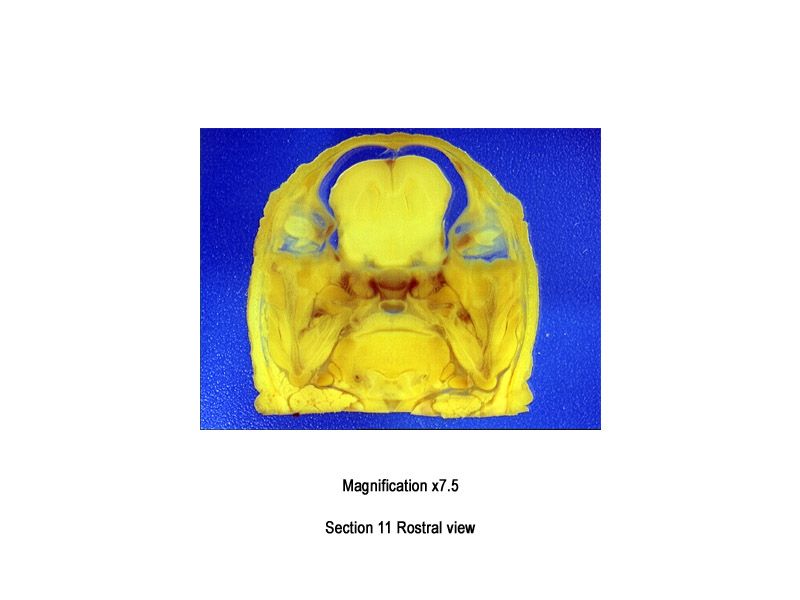

The images below show the normal appearance of Bouin's fluid fixed head sections in specimens at Day 29 of gestation (day mating observed = Day 0).

It is essential that both sides of each section is examined so that structures that exist is several sections can be visualised by the examiner in their mind as 3D.